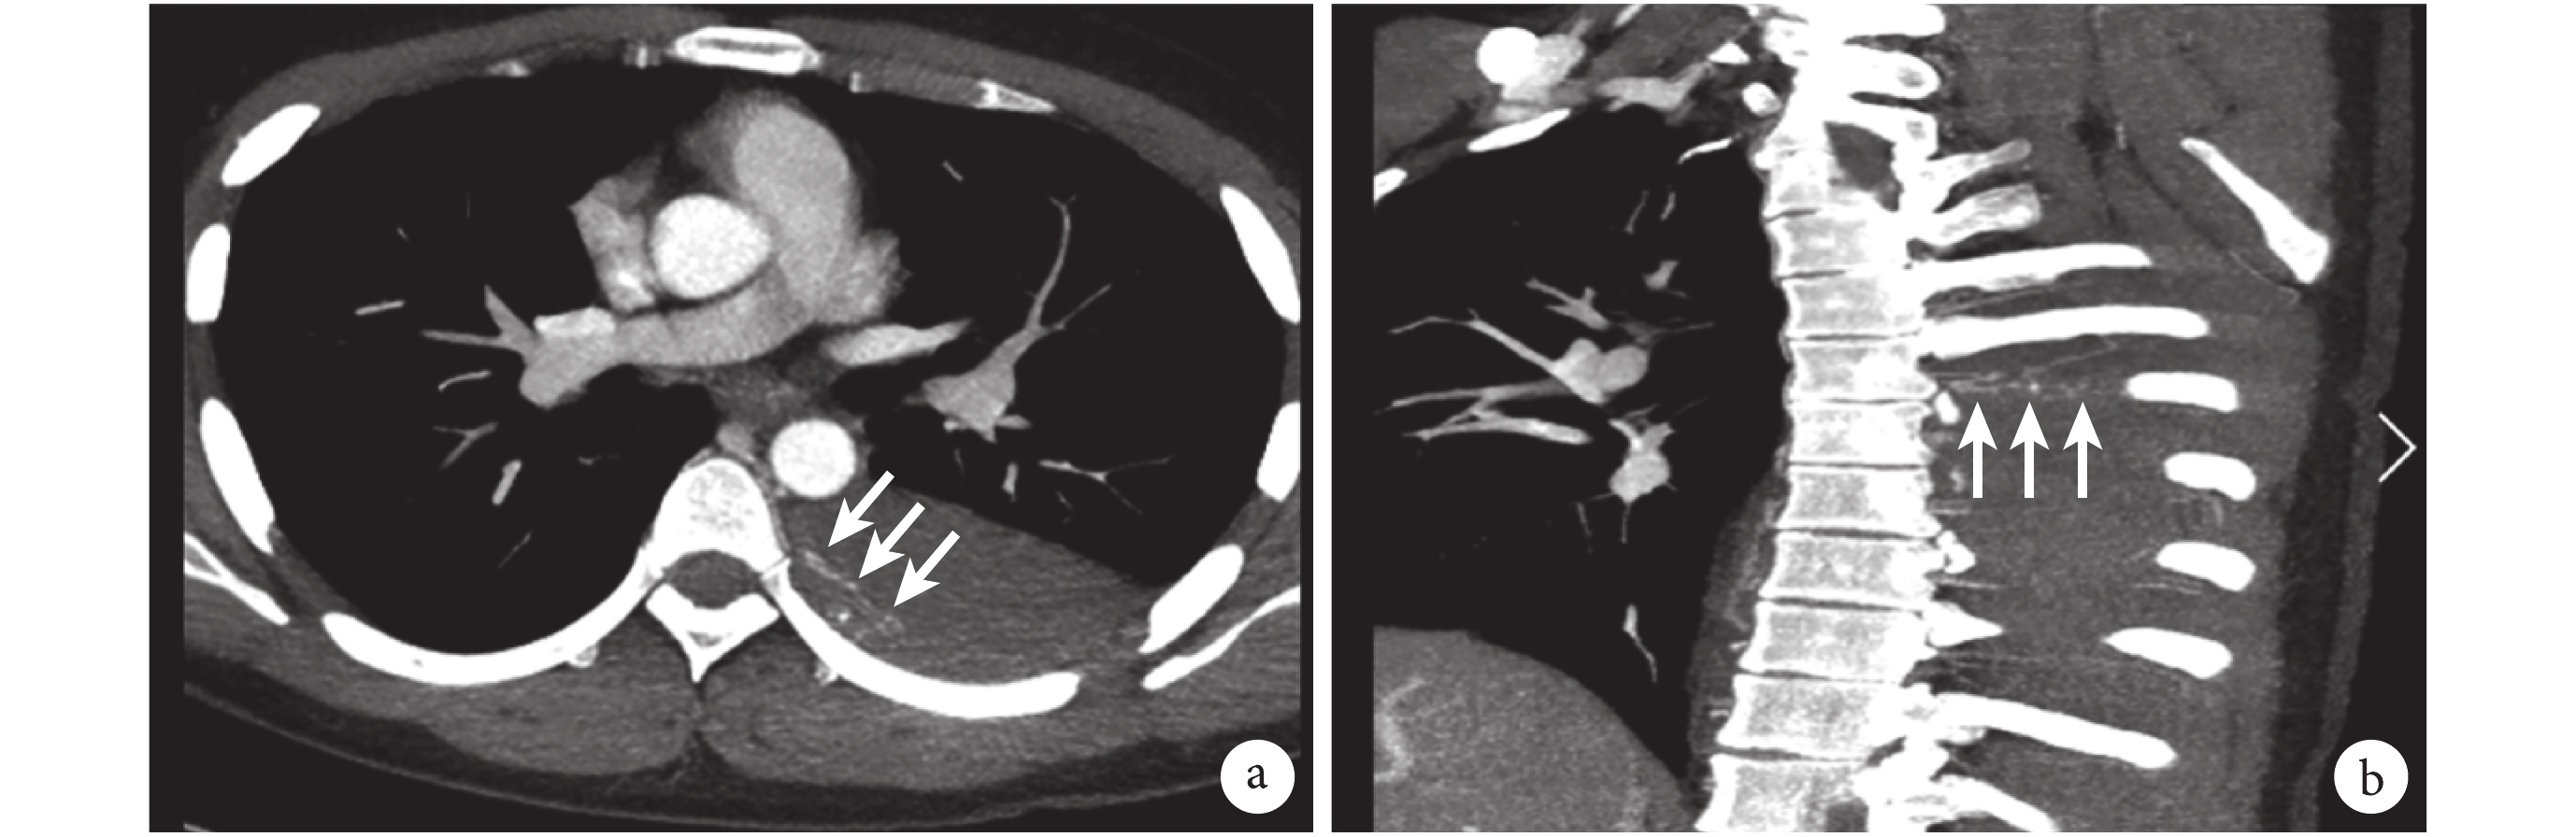

a:橫斷位;b:矢狀位;白色箭頭示來源于降主動脈并沿第 6 肋骨走行的出血分支